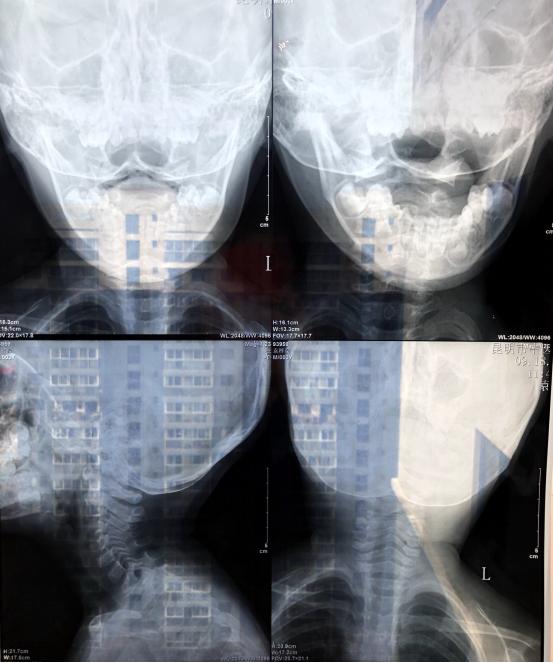

患者今年三岁,有外伤史(从床上摔下来)现在低头的时候头会疼。

李维新 教授:从患者的CT来看,没有明显的骨性结构异常,应该没有大碍。